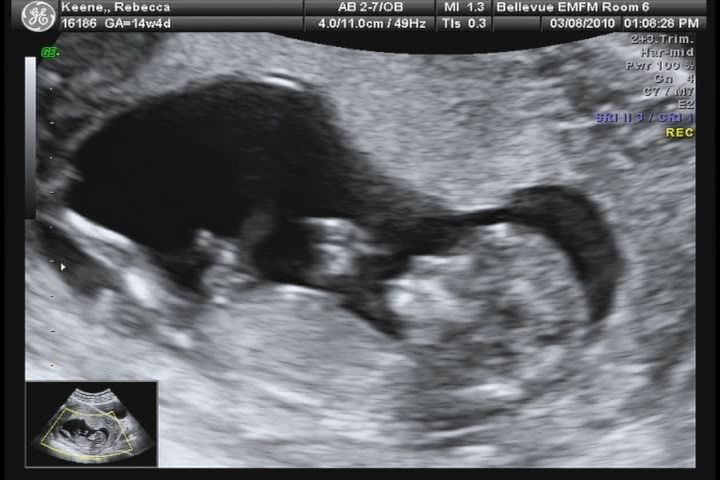

We had our screening appointment today for birth defects, and with it came a wonderful ultrasound. We got some great pictures, and even a DVD. I pulled some of the footage off the video to make a short clip movie – below.

The baby is healthy and strong. We heard the heart beat (160 bpm) and saw Baby 2 hiccupping! Since we believe that it’s a boy, we’re going to continue with “he” instead of “baby 2.”